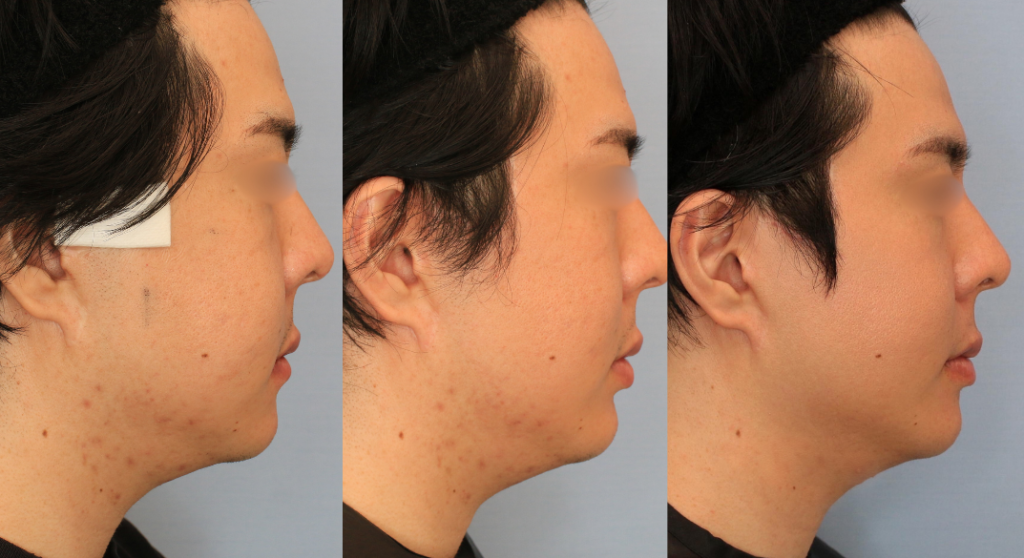

術後1カ月の検診

腫れはほぼきになりません。気にしていた肌荒れが改善したと実感がありました。金属と骨が触れているような感覚や締め付け感がなくなり、よく眠れるようになったとのことです。

横から

術前、10日目、1カ月の経時変化